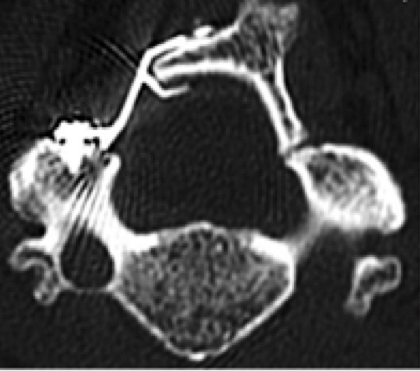

C1-2 fusion

Posterior Cervical Fusion